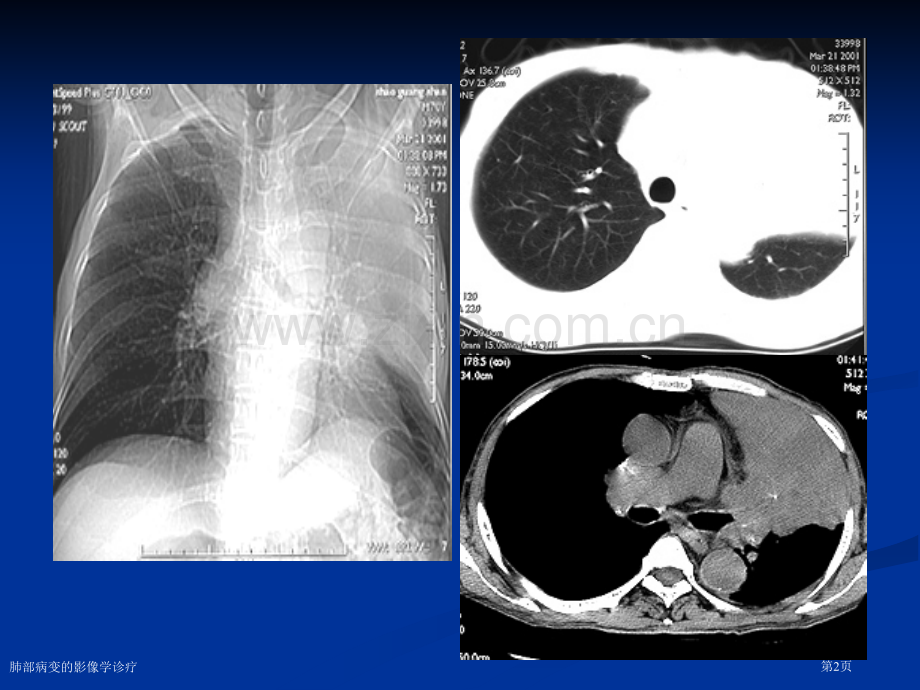

肺部疾病基本征象肺部疾病基本征象 及分析及分析 大连市情谊医院大连市情谊医院 肺部病变的影像学诊疗第1页肺部病变的影像学诊疗第2页 2.阻塞性肺气肿阻塞性肺气肿 1 1)肺野透明度增高肺野透明度增高肺野透明度增高肺野透明度增高 2 2)肺纹理稀、细、直、可有肺大泡)肺纹理稀、细、直、可有肺大泡)肺纹理稀、细、直、可有肺大泡)肺纹理稀、细、直、可有肺大泡 3 3)胸廓各径线增大)胸廓各径线增大)胸廓各径线增大)胸廓各径线增大 4 4)膈位低、动度低)膈位低、动度低)膈位低、动度低)膈位低、动度低 5 5)心脏狭长呈垂位心)心脏狭长呈垂位心)心脏狭长呈垂位心)心脏狭长呈垂位心肺部病变的影像学诊疗第3页阻塞性肺气肿阻塞性肺气肿肺部病变的影像学诊疗第4页二、二、肺部病变肺部病变(一)肺实变(一)肺实变 (二)结节状阴影(二)结节状阴影 (三)肺肿块(三)肺肿块 (四)空洞与空腔(四)空洞与空腔 (五)钙化(五)钙化 (六)肺间质性病变(六)肺间质性病变肺部病变的影像学诊疗第5页肺部病变的影像学诊疗第6页(二)结节状阴影(二)结节状阴影 腺泡结节状影:腺泡结节状影:腺泡结节状影:腺泡结节状影:腺泡实变腺泡实变腺泡实变腺泡实变粟粒状结节影:粟粒状结节影:粟粒状结节影:粟粒状结节影:直径小于直径小于直径小于直径小于4mm4mm 小点状阴影弥散分布小点状阴影弥散分布小点状阴影弥散分布小点状阴影弥散分布 多见于肺间质性病变多见于肺间质性病变多见于肺间质性病变多见于肺间质性病变肺部病变的影像学诊疗第7页CT值:-58HU错构瘤错构瘤肺部病变的影像学诊疗第8页肺部病变的影像学诊疗第9页恶性肿块恶性肿块肺部病变的影像学诊疗第10页厚壁空洞厚壁空洞肺部病变的影像学诊疗第11页肺部病变的影像学诊疗第12页空腔空腔肺部病变的影像学诊疗第13页肺部病变的影像学诊疗第14页肺部病变的影像学诊疗第15页游离性积液游离性积液肺部病变的影像学诊疗第16页气胸气胸肺部病变的影像学诊疗第17页肺部病变的影像学诊疗第18页肺部病变的影像学诊疗第19页支气管胸膜瘘合并脓胸肺部病变的影像学诊疗第20页肺部病变的影像学诊疗第21页肺部病变的影像学诊疗第22页肺部病变的影像学诊疗第23页肺部病变的影像学诊疗第24页肺部病变的影像学诊疗第25页肺部病变的影像学诊疗第26页肺部病变的影像学诊疗第27页